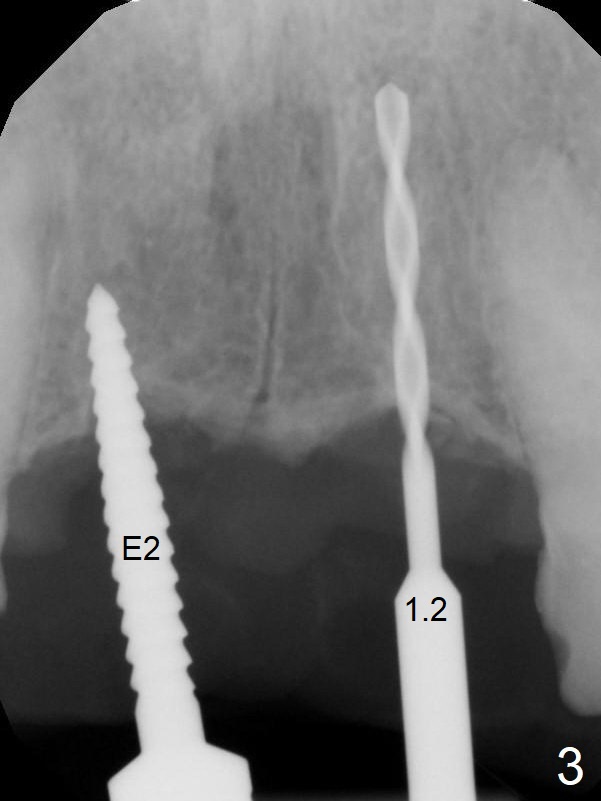

A 45-year-old Spanish woman requests implants to replace #7-10 FPD (Fig.1,2,7). After incision, osteotomy is initiated in the palatal aspect of the crest with 1.2 mm drill and DIO Bone Expanders (E1 (diameter 1.0/1.6 mm),E2 (1.3/2.3 mm), Fig.3,4). Following adjustment of the trajectory (to avoid invasion of the Incisive Canal (Fig.2 *) and use of E3 (1.7/3.1 mm), two of 3.5x11.5 mm HIOSSEN implants are placed with satisfactory stability (Fig.5). With Vanilla graft (Fig.5 *) placed over the palatally-exposed coronal threads, the flaps are approximated (Fig.6). The FPD is recemented temporarily (Fig.7).